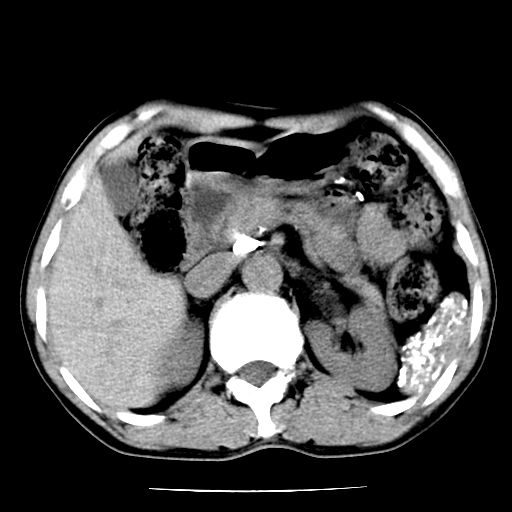

男,59岁,“结核性胸膜炎”30余年,胸部经常疼痛,多次x检查提示“肺部”炎症。腹部疼痛5日,b超提示:“肝内短管结石,余显示不清,建议进一步检查。”

两肺结核并右侧胸腔积液;脾脏、腹腔及腹膜后淋巴结结核[陈旧性];肝内胆管结石

胸部腹部都是结核(双肺。纵隔淋巴结,肝脏,脾脏,肠系膜)

两肺结核并右侧胸腔积液;脾脏、腹腔及腹膜后淋巴结结核[陈旧性];肝内胆管结石。直肠息肉?